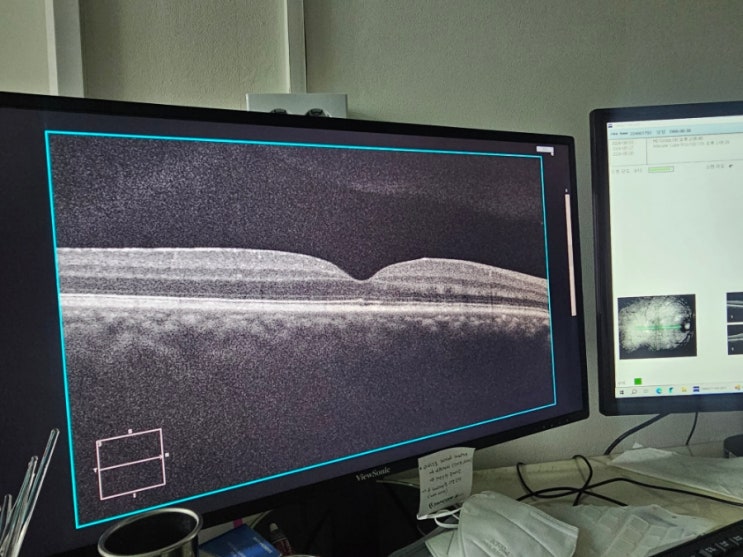

산동검사 안구충격 충돌로 인한 시력문제 공안과 후기

산동검사 안구충격 충돌로 인한 시력문제 공안과 후기 ㅎㅇ 소셜마스터 후니훈 오늘도 여전히 좋아지지 않...